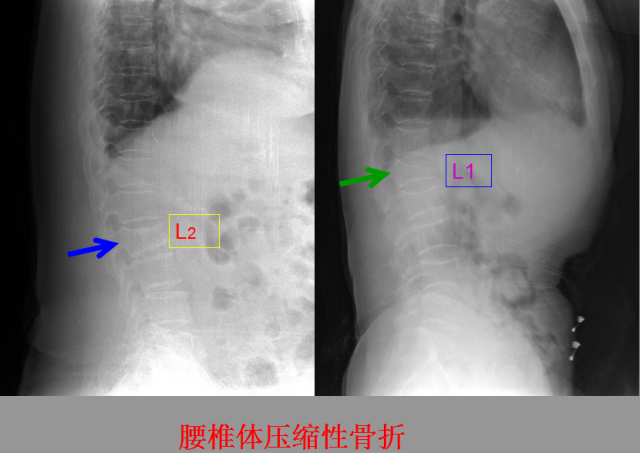

骨折篇

01

定义:骨折{Fracture}是指骨的完整性和连续性的折裂或粉碎。包括创伤性骨折、疲劳性骨折和病例理性骨折。 临床上以创伤性骨折*常见。